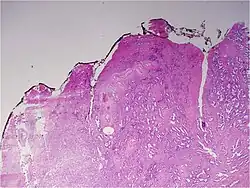

Histologic patterns

A pathologist microscopically examines the biopsy specimen for certain "Gleason" patterns. These Gleason patterns are associated with the following features:

- Pattern 1 – The cancerous prostate closely resembles normal prostate tissue. The glands are small, well-formed, and closely packed. This corresponds to a well differentiated carcinoma.

- Pattern 2 – The tissue still has well-formed glands, but they are larger and have more tissue between them, implying that the stroma has increased. This also corresponds to a moderately differentiated carcinoma.

- Pattern 3 – The tissue still has recognizable glands, but the cells are darker. At high magnification, some of these cells have left the glands and are beginning to invade the surrounding tissue or having an infiltrative pattern. This corresponds to a moderately differentiated carcinoma.

- Pattern 4 – The tissue has few recognizable glands. Many cells are invading the surrounding tissue in neoplastic clumps. This corresponds to a poorly differentiated carcinoma.

- Pattern 5 – The tissue does not have any or only a few recognizable glands. There are often just sheets of cells throughout the surrounding tissue. This corresponds to an anaplastic carcinoma.

In the present form of the Gleason system, prostate cancer of Gleason patterns 1 and 2 are rarely seen. Gleason pattern 3 is by far the most common.

The Gleason grade is based on tissue architectural patterns rather than purely cytological changes. These tissue patterns are classified into 5 grades, numbered 1 though 5. Lower numbers indicate more differentiation, with pattern 5 being the least differentiated.[4][7] Differentiation is the degree to which the tissue, in this case the tumor, resembles native tissue. Greater resemblance (lower grade) is typically associated with a better prognosis.

However, the Gleason score is not simply the highest grade (least differentiated) pattern within the tumor. Rather, it is a combination of the most two most frequent patterns seen. This recognizes that prostatic carcinomas have multiple patterns and that prognosis is more accurately determined by adding the scores of the two most prevalent patterns. Using this system, the grades of the most prevalent and second most prevalent patterns (if at least 5% of the total), are added together to yield the overall Gleason score.[4][7]